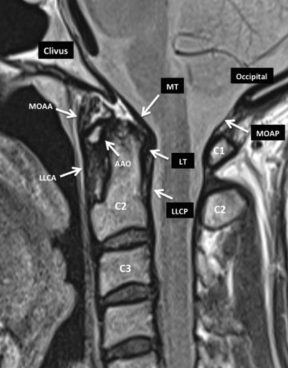

Algunos autores señalan la existencia de un grupo de ligamentos accesorios, de menor desarrollo, que si bien son identificables durante disecciones anatómicas, no son visualizados en estudios de RM de alta resolución. Destacaremos los ligamentos más importantes en la fisiología de la región e identificables en los estudios de RM (►Fig. 7, ►Fig. 8, ►Fig. 9 y ►Fig. 10).

RM, secuencia DP, plano sagital. Corte sagital de la UCC idéntico al de la figura 8 pero en secuencia DP que resalta las estructuras ligamentarias. Se destaca la identificación del LT situado entre la apófisis odontoidea de C2 y la MT. Abreviaciones: AAO, articulación atloido-odontoidea; C1, 1ª vértebra cervical; C2, 2ª vértebra cervical; C3, 3ª vértebra cervical; LLCA, ligamento longitudinal común anterior; LLCP, ligamento longitudinal común posterior; LT, ligamento trasverso; MOAA, membrana occipito- atloido-axoidea; MT, membrana tectoria; MOAP, membrana occipito- atloidea posterior.